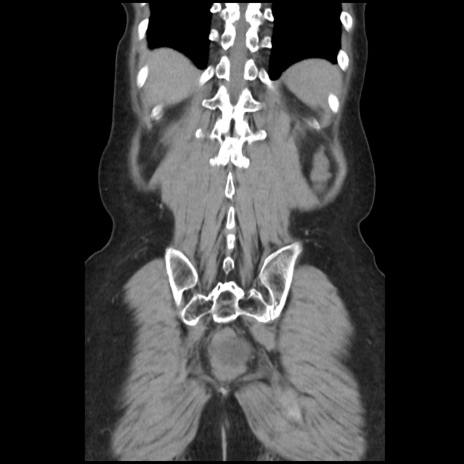

症例32(冠状断像)

【症例】40歳代 女性

【主訴】上腹部痛、嘔気・嘔吐

【現病歴】約9時間前頃から急に上腹部痛、嘔気、嘔吐が出現。改善しないため救急要請。

【既往歴】子宮頚癌(広汎子宮全摘術、放射線療法)、腸閉塞

【身体所見】腹部:平坦、軟、腸雑音亢進、上腹部を中心に腹部全体に圧痛あり。

【データ】WBC 8400、CRP 0.03